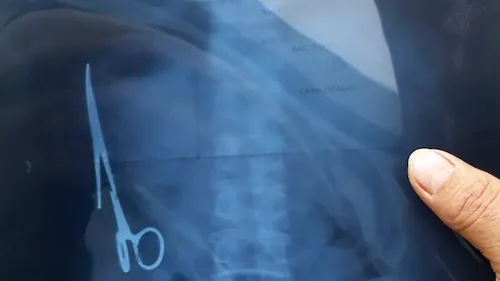

Elle vivait depuis 20 ans avec une paire de ciseaux chirurgicaux...